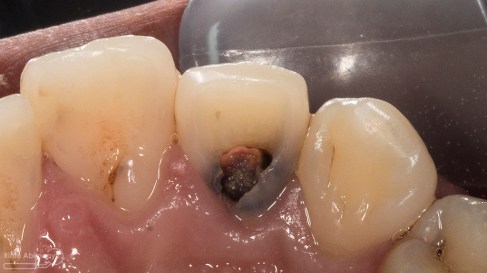

Tentang gigi 12 yang mengalami karies di palatal. Jadi pasien datang mengeluhkan di belakang giginya terasa ada lubang dan sering kemasukan makanan. Gigi tersebut dulu pernah sakit tapi sekarang sudah tidak terasa lagi. Gigi itu belum pernah ditambal sama sekali.

Setelah saya lihat kondisinya seperti ini…

dan ini hasil ronsen nya..

Dari dua informasi klinis maupun radiografis saya sampaikan ke pasien bahwa kavitasnya sudah mengenai ruang saraf dari gigi tersebut, sehingga tidak mungkin langsung ditambal biasa. Singkat cerita saya jelasin deh tuh panjang lebar kenapa gak bisa langsung ditambal ( karena kalo saya tulis bisa kepanjangan… jelasin nya aja sekitar 20 menitan hehehehe )